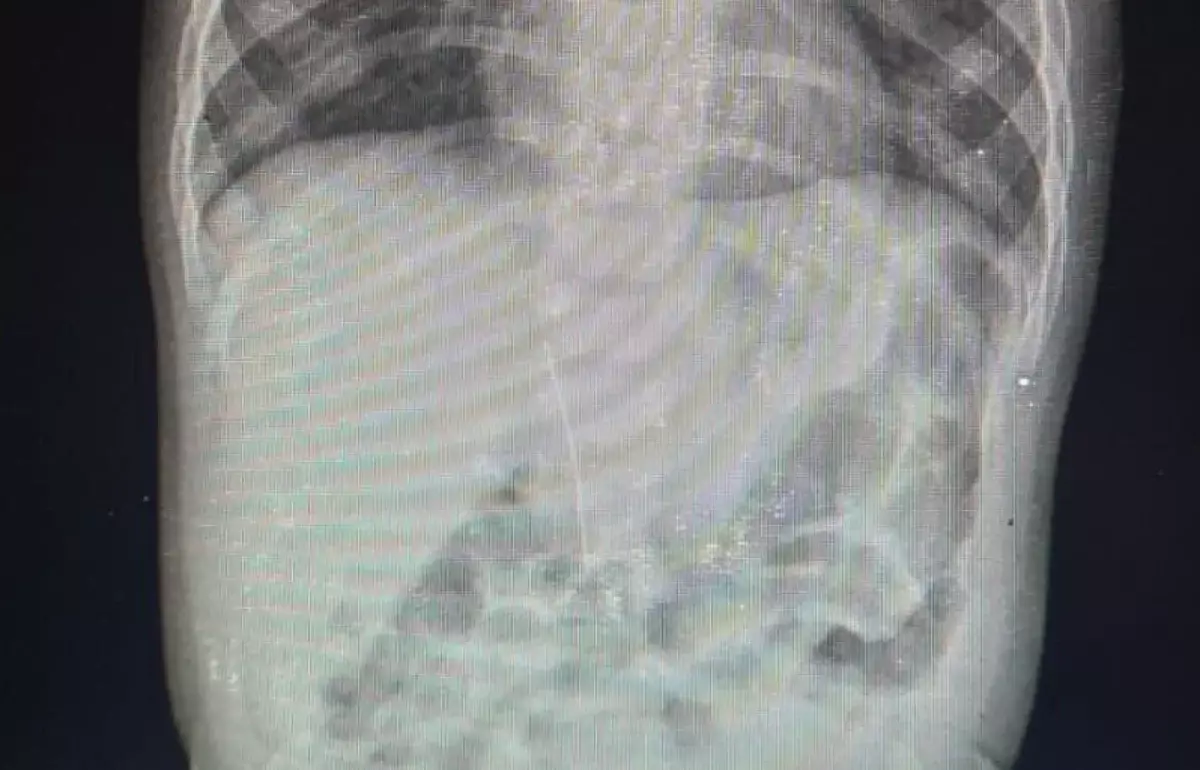

Иглу нашли в брюшной полости младенца в Туркестане